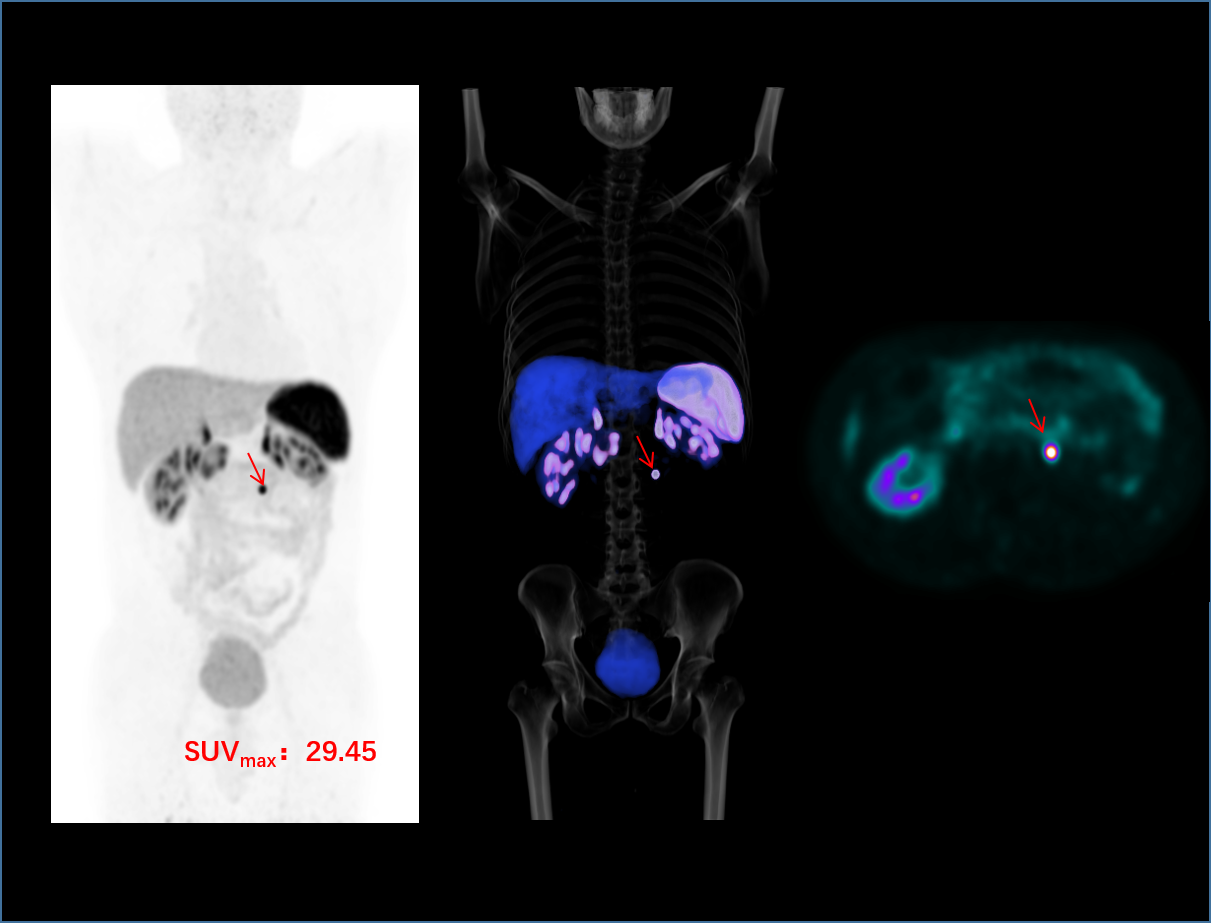

超清显像

2.9mm

超清NEMA分辨率成像

TOF + PSF

微小病灶无以遁形